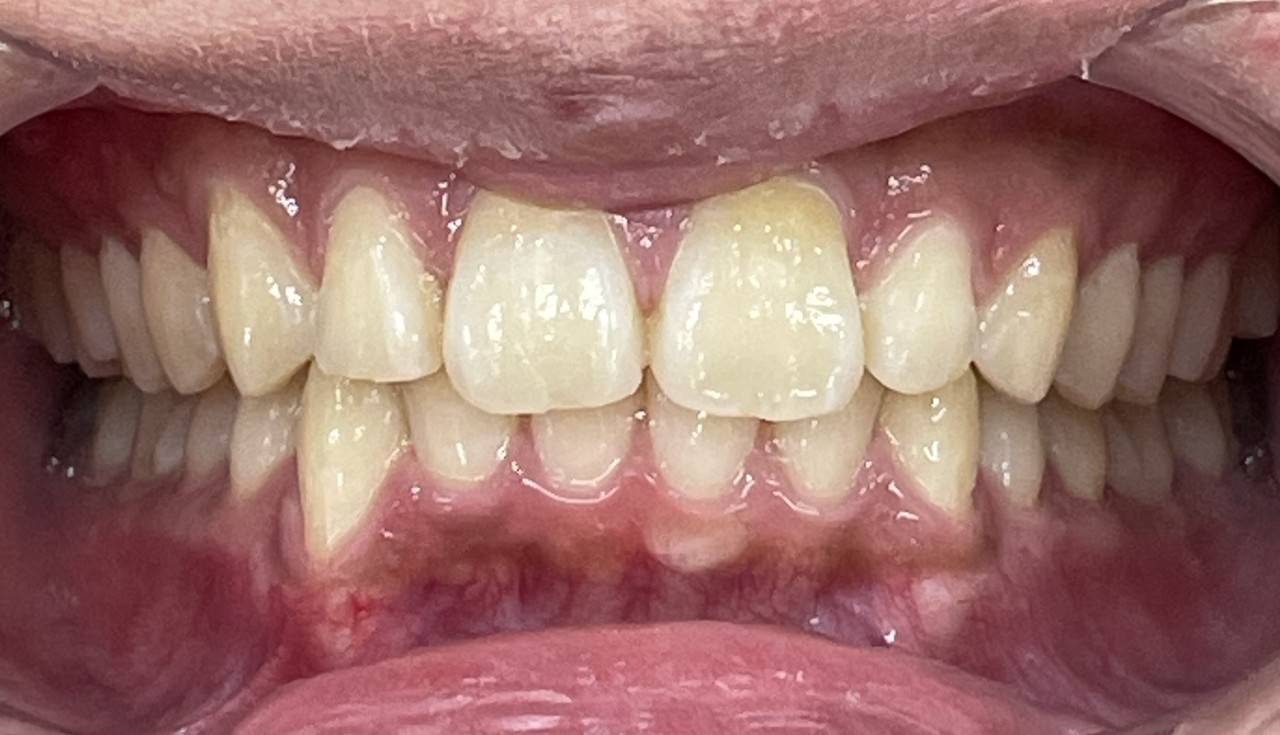

Before

After

矯正の種類 / invisalign GO

年齢・性別 / 30代女性

主訴  /  叢生、交叉咬合

治療期間 / 17ヶ月

費用 / 簡易検査 5,000円(税別) 精密検査 30,000円(税別)

両顎マウスピース 450,000円(税別) 両顎リテイナー料 60,000円(税別)

※マウスピース交換時別途調節料5,000円(税別)

副作用 / 口内炎・歯の移動に伴う痛み・知覚過敏 ※数日で収まる場合が多いです

リスク / 後戻り防止の為、夜のみマウスピースで保定を指示